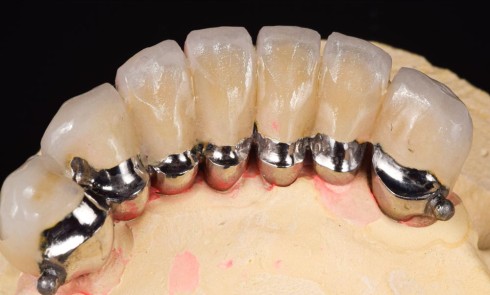

Article réservé à nos abonnés Prise en charge occluso-prothétique des conséquences orales et maxillo-faciales du bruxisme : apport de la prothèse amovible de recouvrement

Le bruxisme est défini comme le grincement parafonctionnel des dents, ou encore comme une habitude orale composée de tapotements, de...